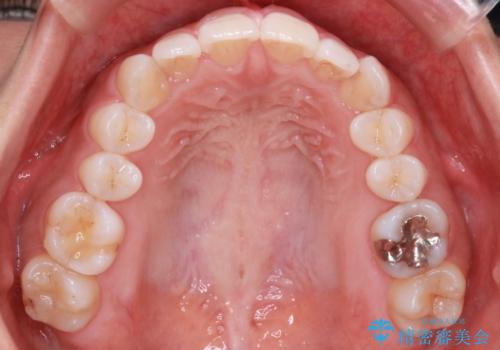

【インビザライン】前歯のねじれを治したい

- 前歯のガタガタを主訴に来院されました。

叢生の量は軽度でしたが臼歯の遠心移動を行い、インビザラインにて治療をしました。

叢生の改善に必要なスペースは遠心移動やIPRで作ることが可能です。今回は遠心移動をメインにスペースを作って叢生の改善を行いました。